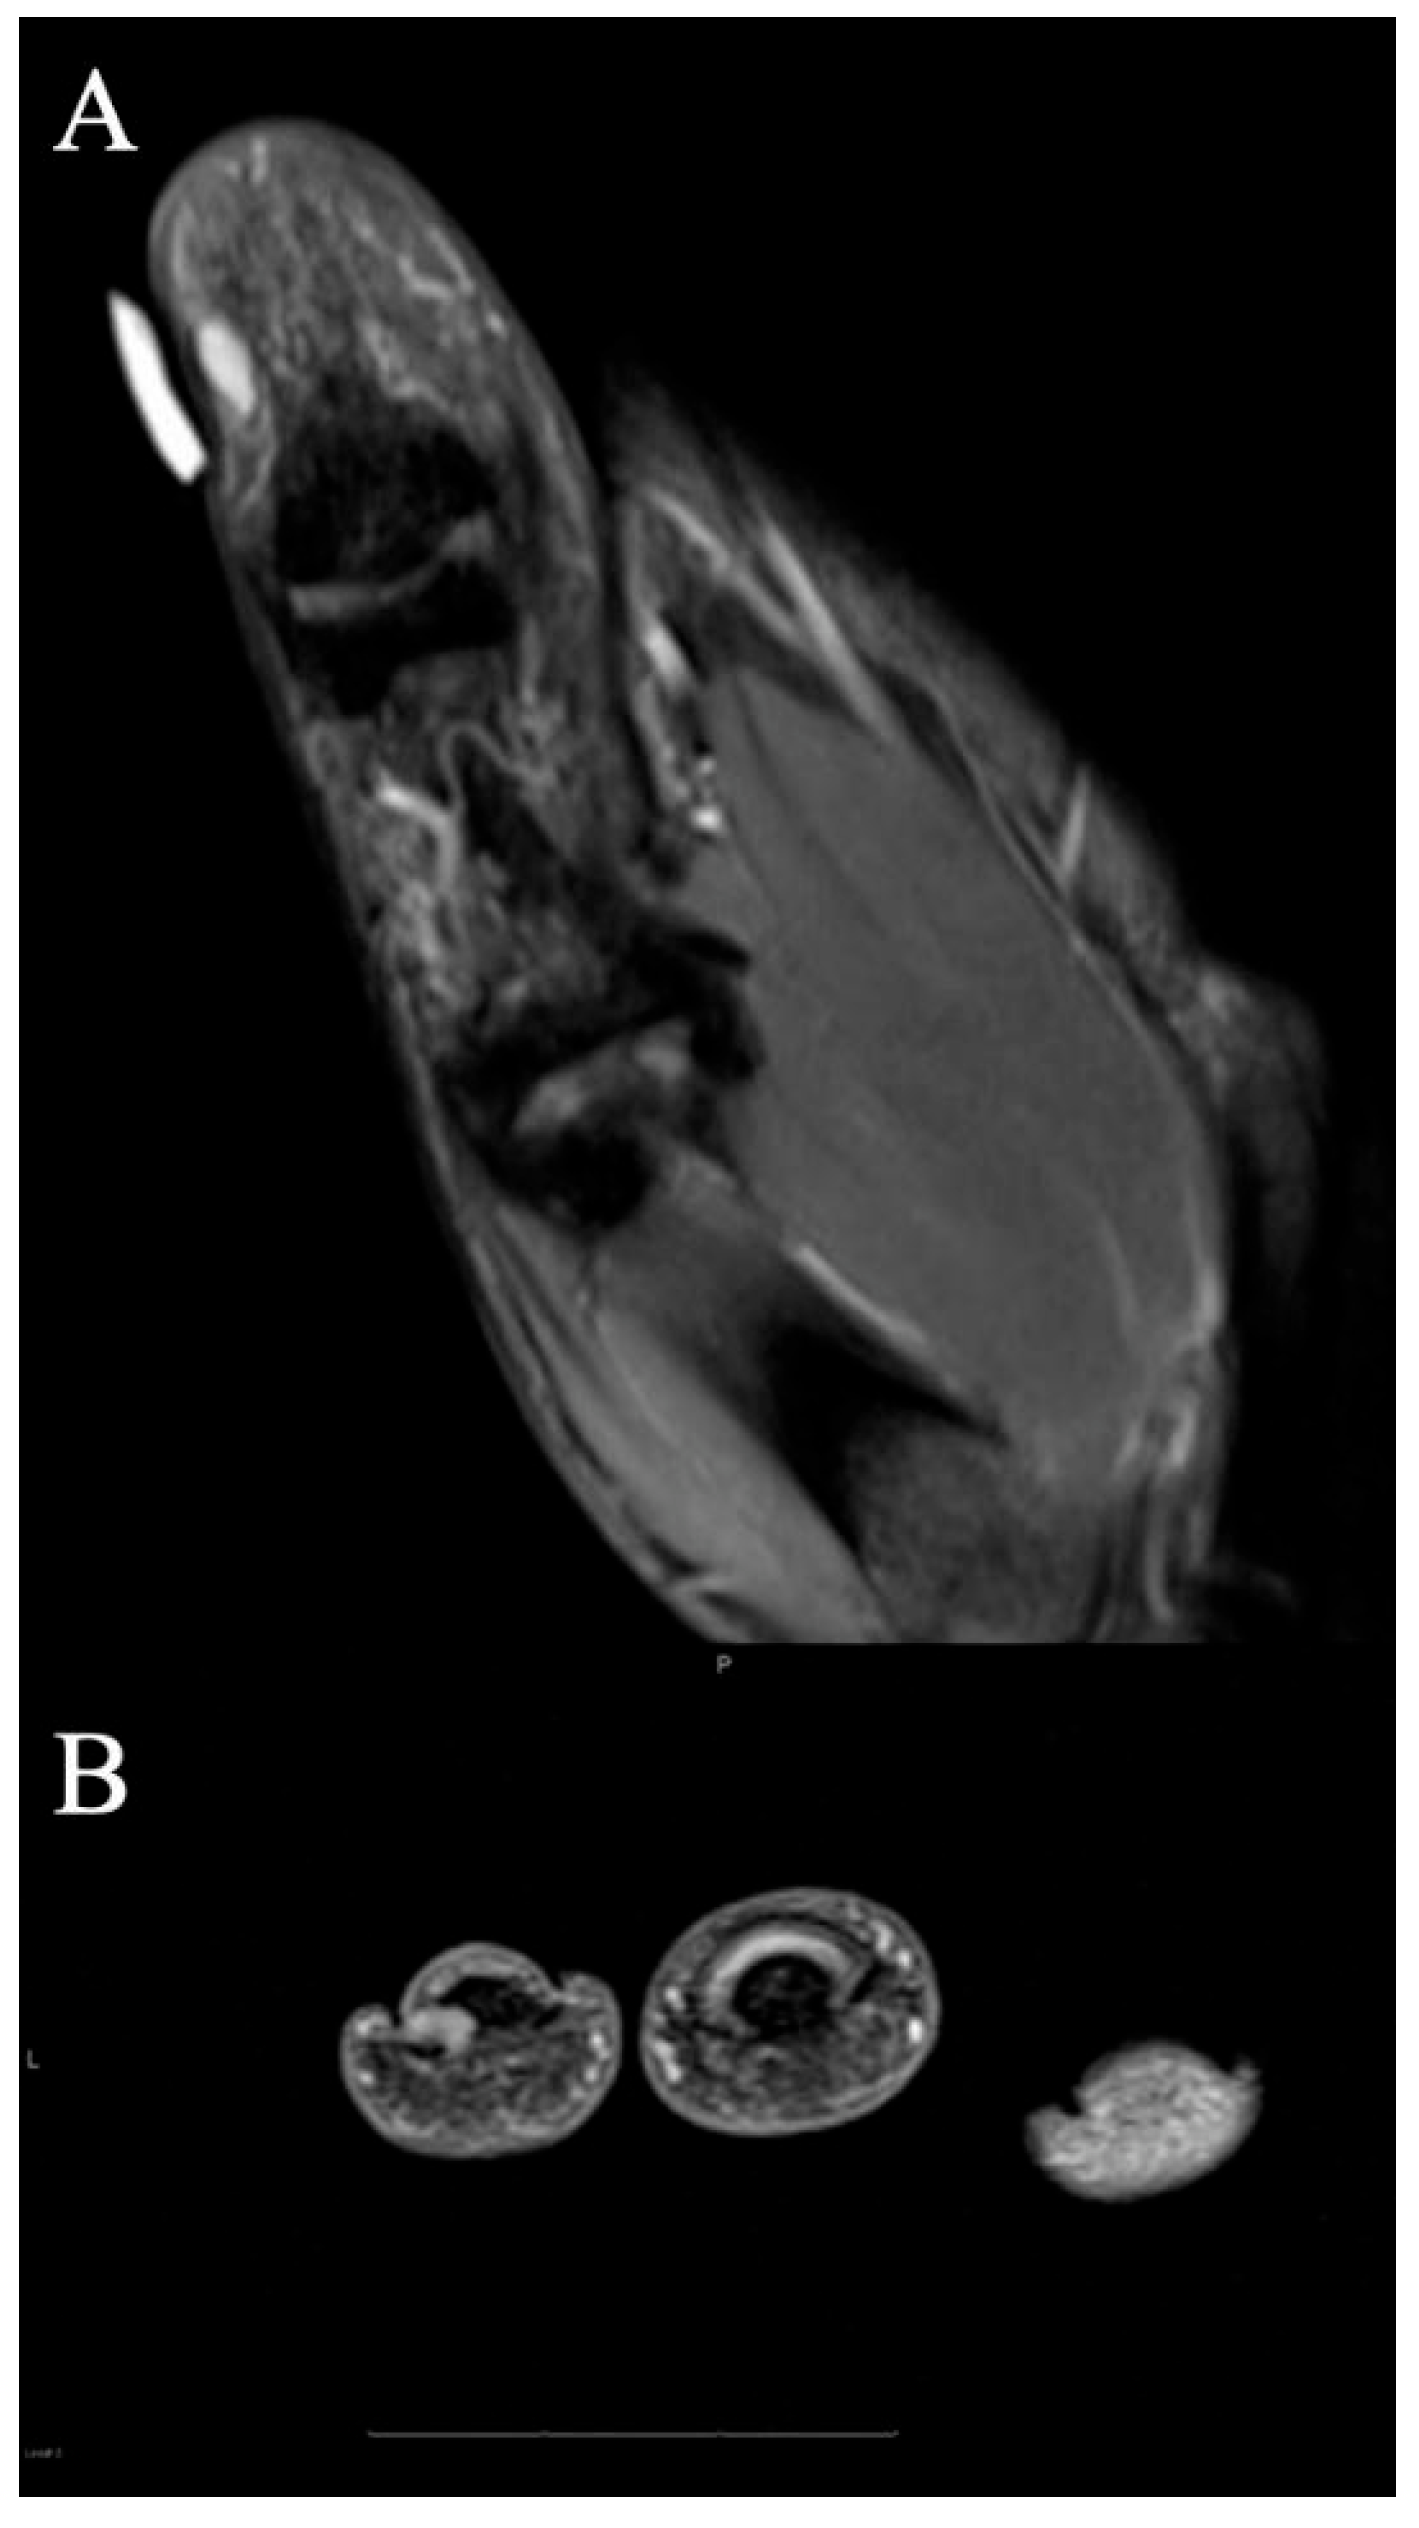

2.6. Vascular Tumors and Malformations

2.6.1. Clinical Features

2.6.2. Imaging Appearance